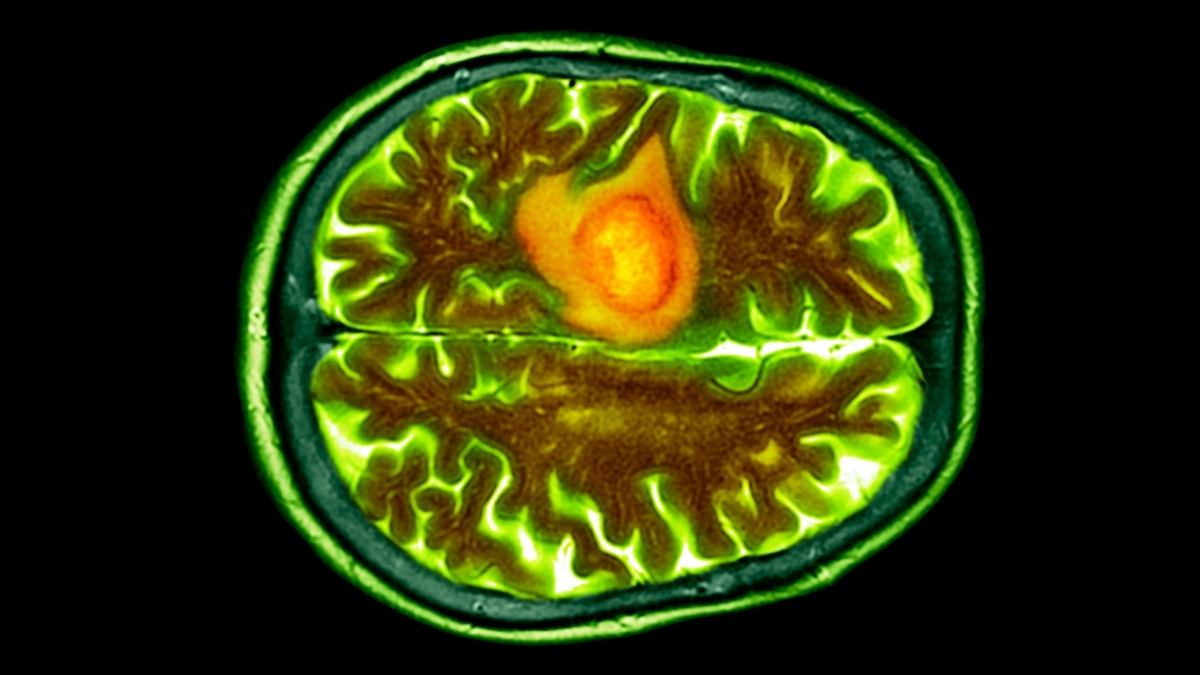

Researchers have developed nasal drops that travel along the nerves of the nose into the central nervous system to fight the deadliest brain cancer.

Preliminary test results reveal that the medication safely reached its target, helping protect…